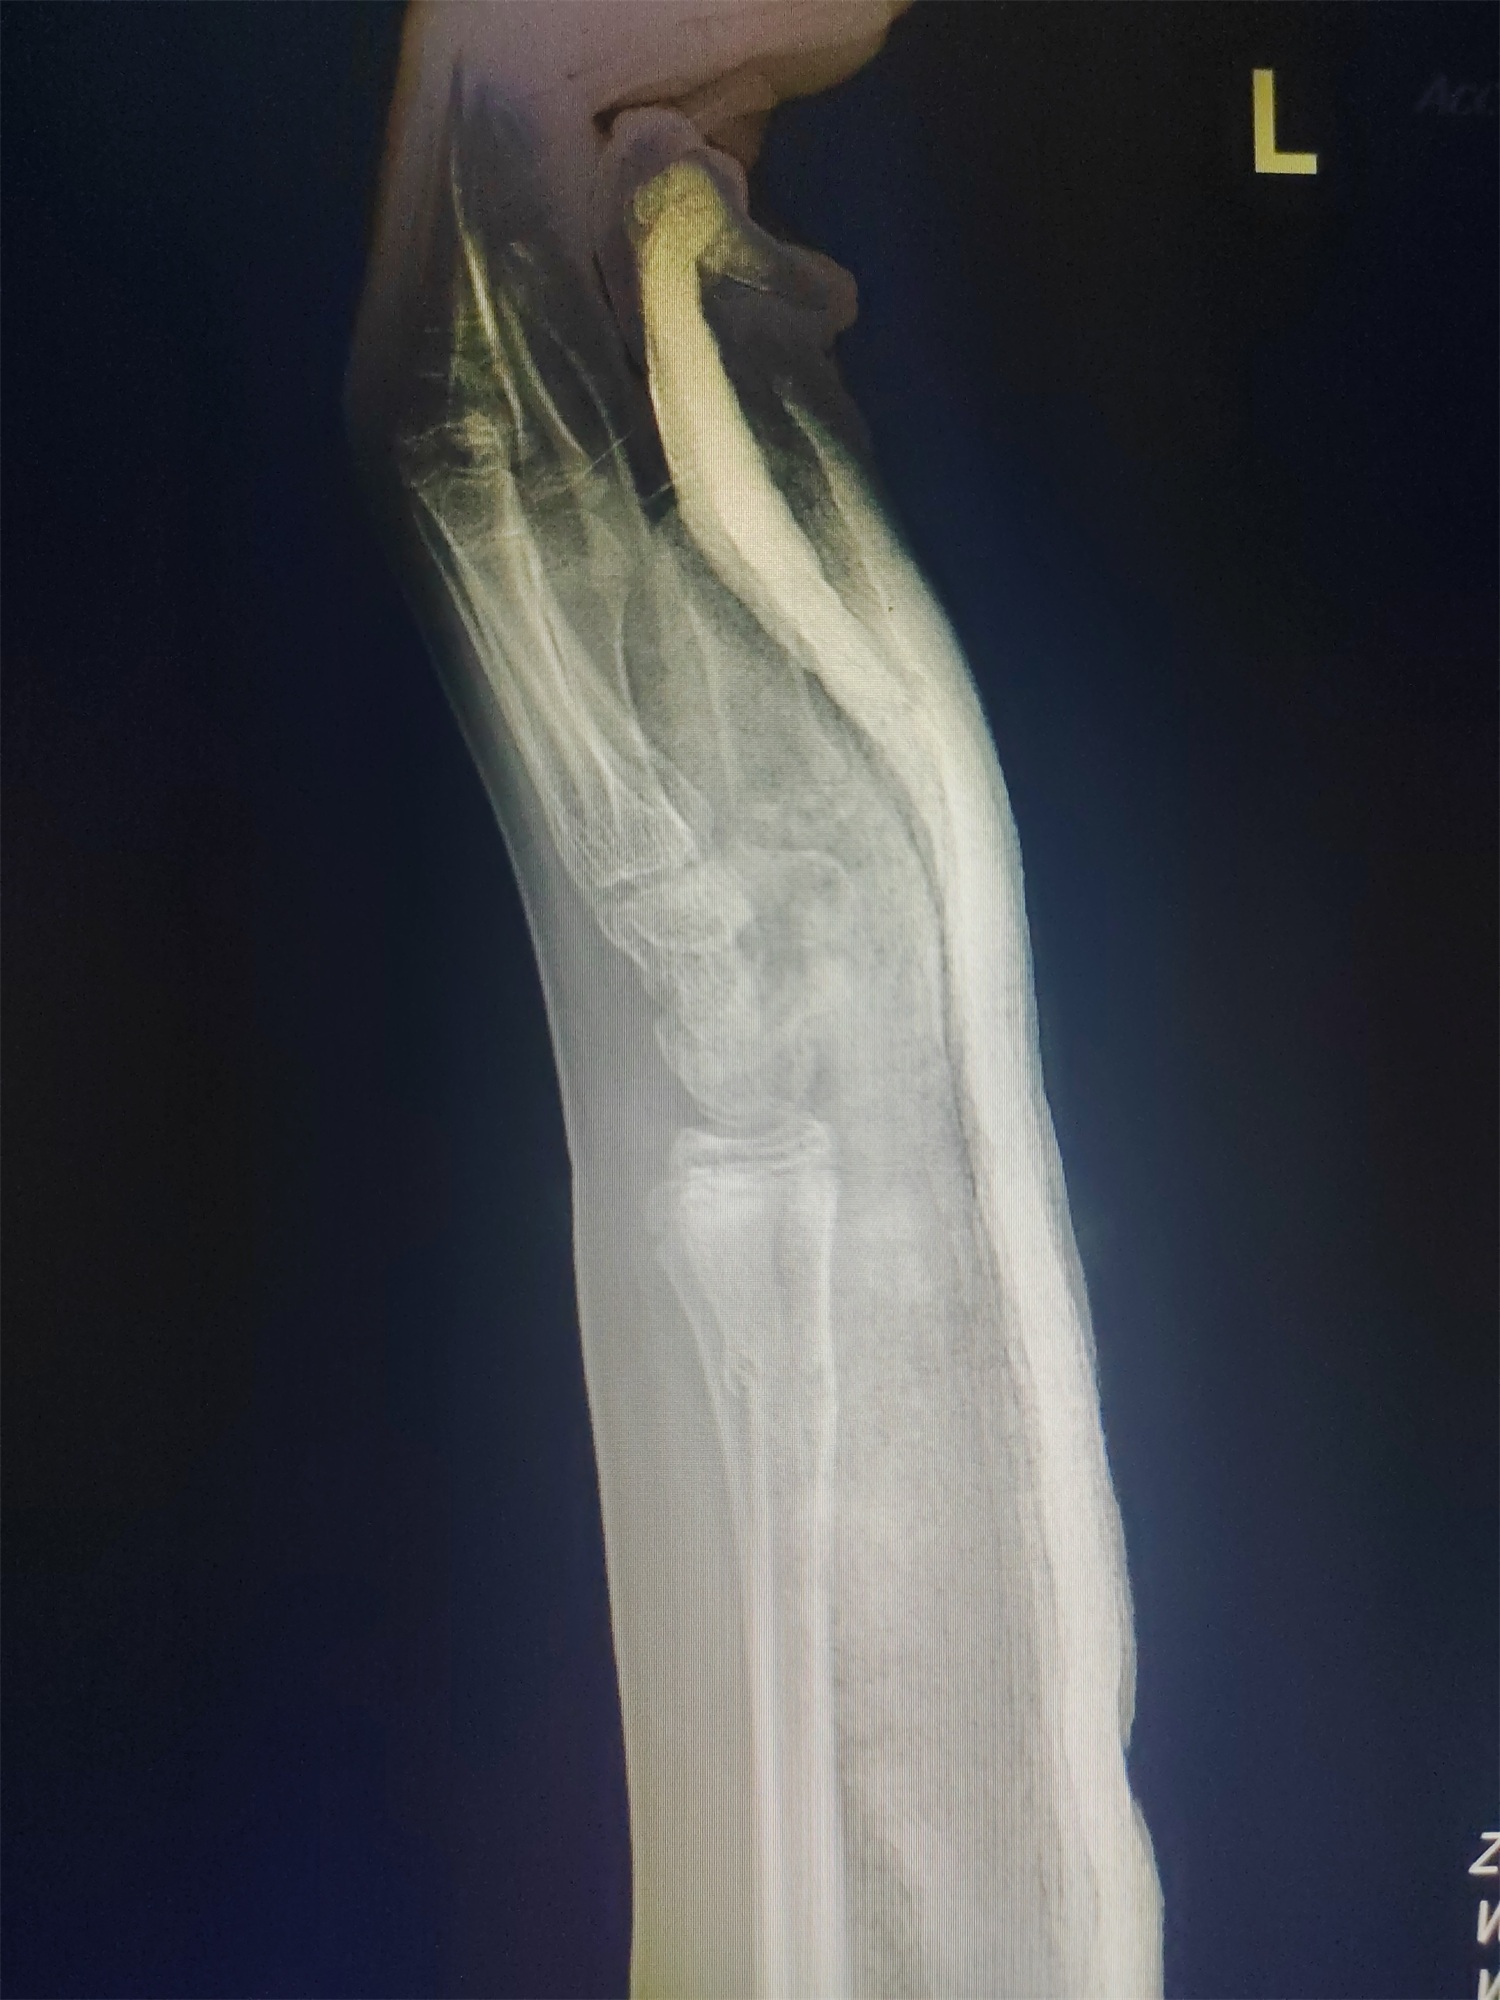

13岁的男孩小陈这几天非常苦恼,因为他的左前臂上长满了红疹。这事儿还得从一个多月前说起,那时他正和同学打闹,结果一不小心被推倒在地,单手撑地的瞬间,剧痛从腕处袭来。医院诊断结果显示:左侧桡骨中下段骨折。

检查结果出来后,医生选择保守治疗,给小陈的手腕做了传统的石膏托外固定。

小陈戴上石膏